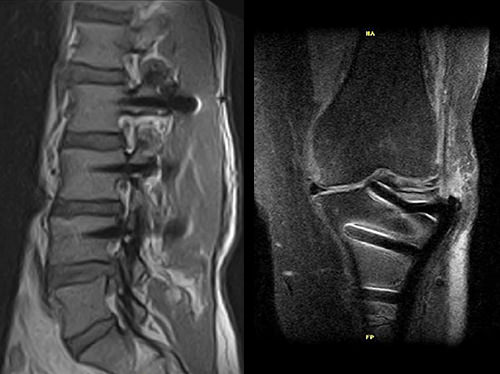

Pacienti s kovovými implantáty tvoří stále větší část populace MRI. Magnifico MRI je optimální řešení, protože systém má přirozeně nízkou úroveň citlivosti na kovy ve srovnání s tradiční MRI.

Společně s vyhrazenými MAR sekvencemi nabízí Magnifico vysoce kvalitní diagnostiku také v přítomnosti většiny implantátů

Klinické snímky